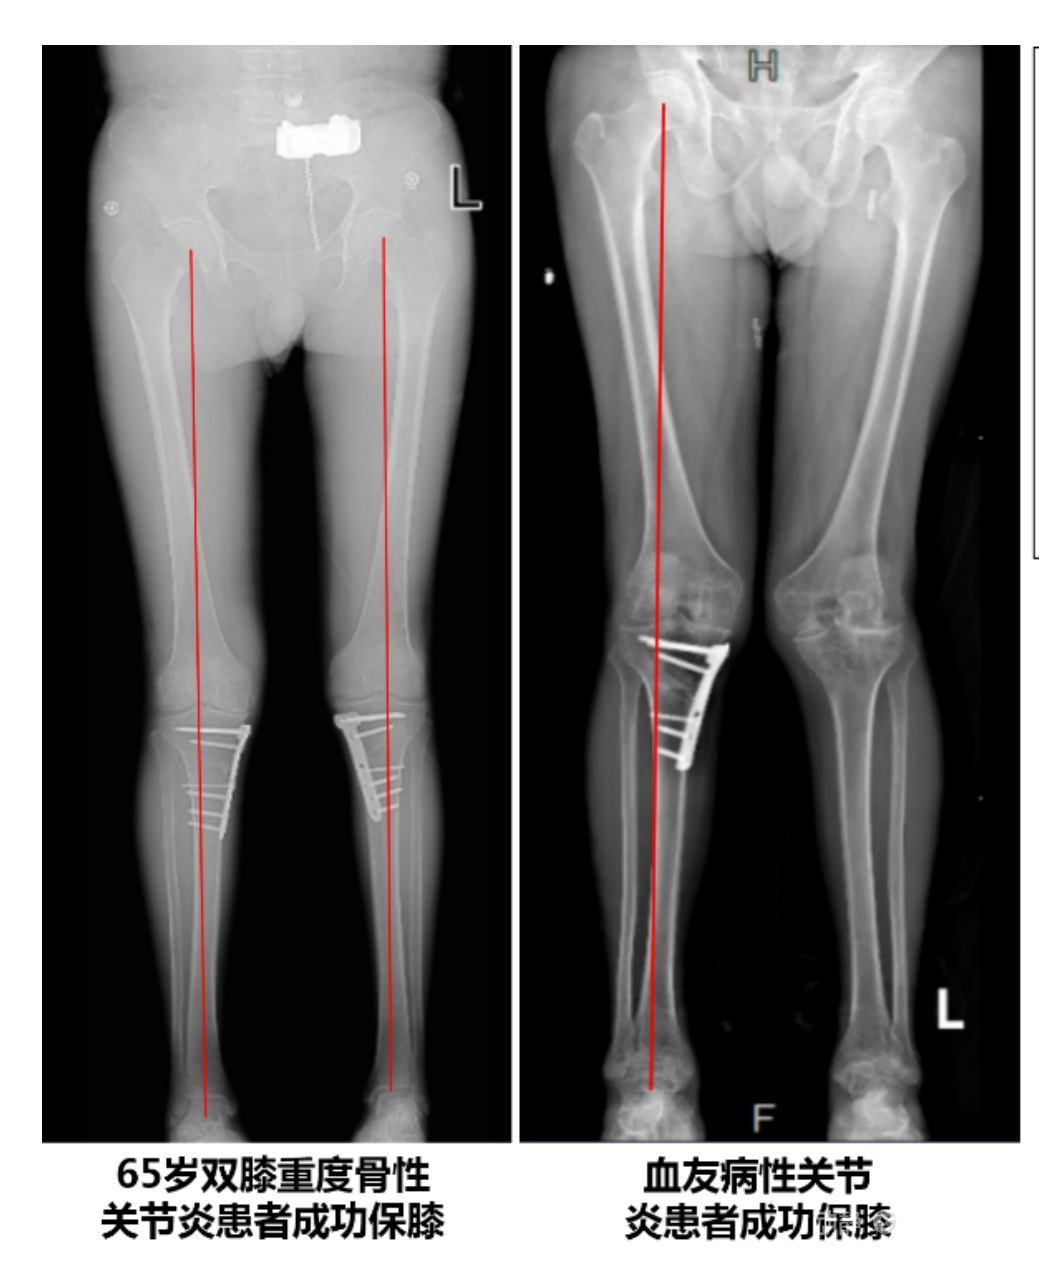

4.2 APTT-HTO脛骨高位截骨術(shù)

2025年7月,貴州醫(yī)科大學(xué)附屬醫(yī)院骨科團(tuán)隊原創(chuàng)研發(fā)的腘肌前結(jié)節(jié)中脛骨高位截骨保膝術(shù)(Anterior Popliteus Transtibial Tuberosity-High Tibial Osteotomy, APTT-HTO)及其提出的脛骨結(jié)節(jié)分區(qū)與腘肌保護(hù)理論,登上了國際頂尖學(xué)術(shù)舞臺。該成果在全球最具影響力的專業(yè)會議之一——日本骨科協(xié)會第98屆年會上進(jìn)行了兩次學(xué)術(shù)發(fā)言。[8]

該手術(shù)具有經(jīng)皮微創(chuàng)、保留原生膝關(guān)節(jié)結(jié)構(gòu)、符合階梯治療原則等優(yōu)勢,通過調(diào)整下肢力線可促進(jìn)部分軟骨再生,術(shù)后關(guān)節(jié)功能接近正常(如下蹲、爬山),患者還能從事中重體力勞動。相比其他術(shù)式,其有效規(guī)避了髕骨低位、血管損傷、合頁骨折等潛在并發(fā)癥。

目前,APTT-HTO技術(shù)已成功應(yīng)用于千余名患者,幫助保留自身膝關(guān)節(jié)。此類保膝手術(shù)適用于單間室膝關(guān)節(jié)炎患者(如 “羅圈腿”),核心是通過調(diào)整力線糾正畸形,減輕磨損間室壓力、發(fā)揮健康間室作用,延長膝關(guān)節(jié)壽命。若出現(xiàn)膝關(guān)節(jié)疼痛、保守治療無效且X線顯示關(guān)節(jié)間隙部分狹窄,建議及時就醫(yī)評估是否適合手術(shù)。